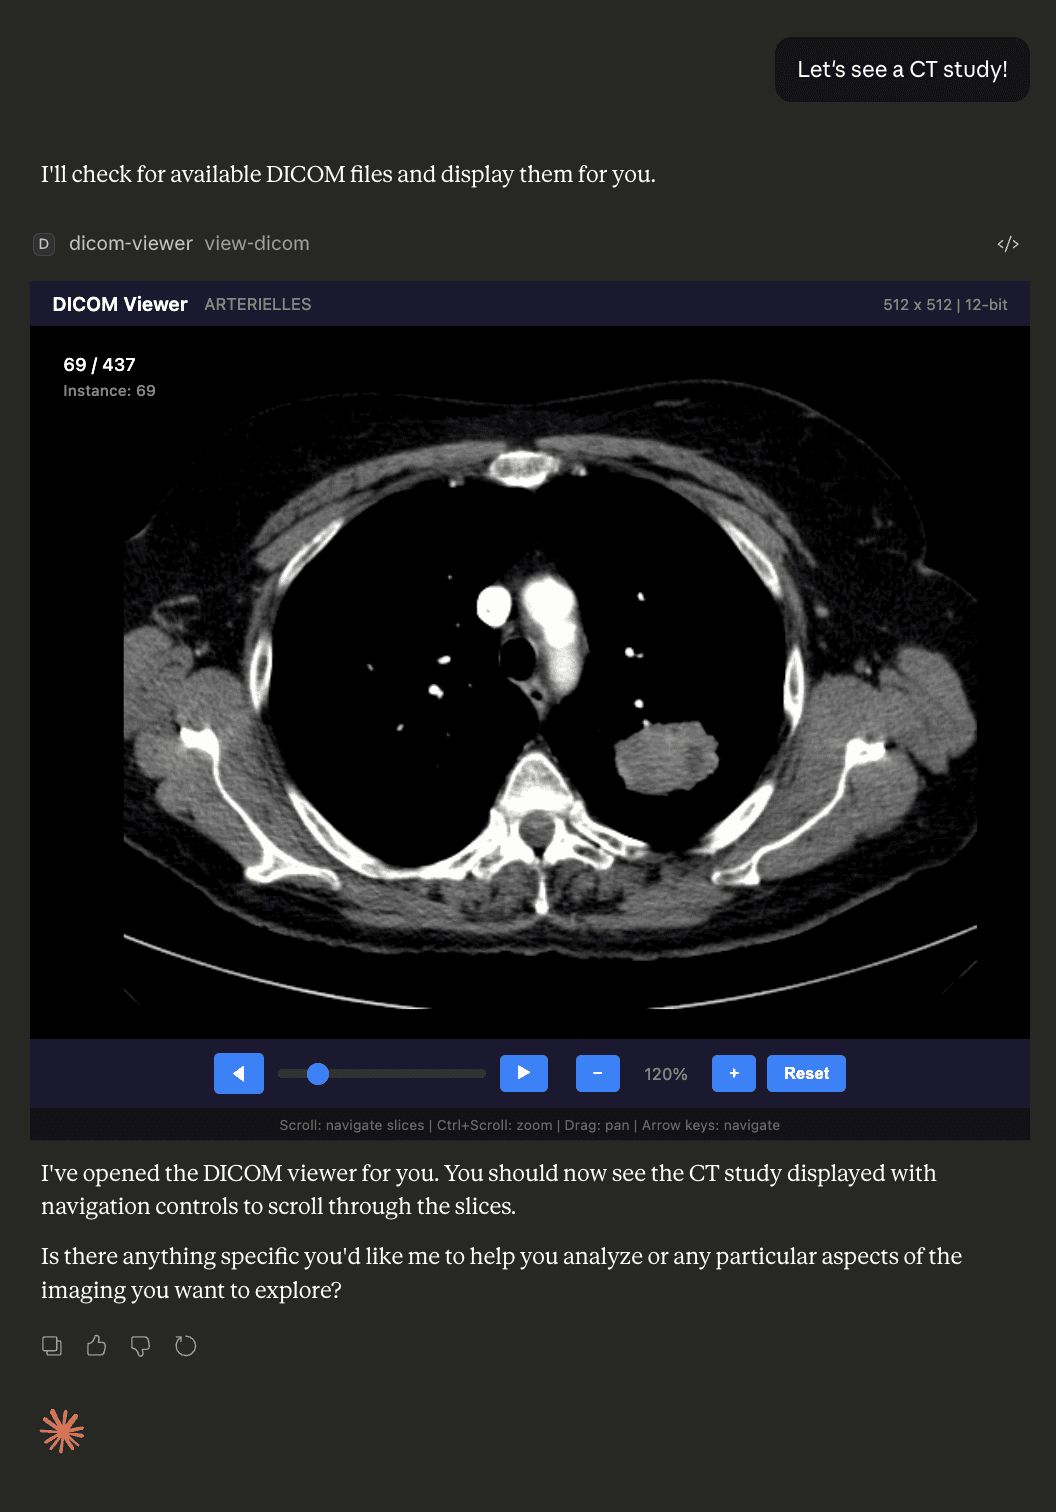

View DICOM medical image series directly inside Claude Desktop — slice navigation, pan/zoom, and metadata display without leaving your AI interface.

DICOM Viewer MCP is a prototype MCP App that lets you load and navigate medical imaging studies (.dcm files) directly within Claude Desktop. It processes DICOM files server-side using dicom-parser and sharp, converts pixel data to PNG with proper window/level handling, and serves the result as an interactive HTML resource — bypassing Content Security Policy restrictions entirely.

- In-interface DICOM rendering — no external viewer needed; images appear inside Claude Desktop

- Series navigation — scroll wheel, slider, previous/next buttons, and Home/End keyboard shortcuts to move through slices

- Pan and zoom — Ctrl+scroll to zoom, click-and-drag to pan, reset button to restore default view